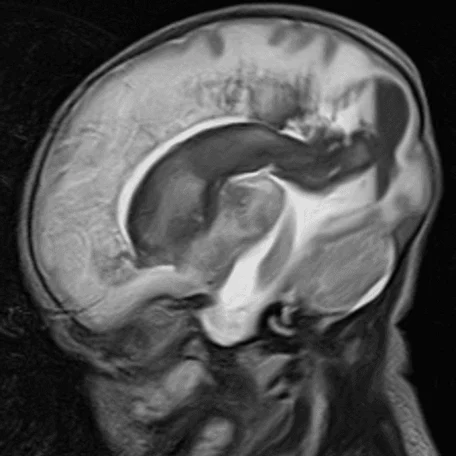

Внутрижелудочковые кровоизлияния

Чаще возникают у недоношенных новорожденных. Основным источников ВЖК служат сосуды эпендимы мозга и сосудистые сплетения. Способствующие факторы: затяжные или быстрые роды, перинатальная гипоксия, коагулопатии, нестабильность гемодинамики у новорожденного.